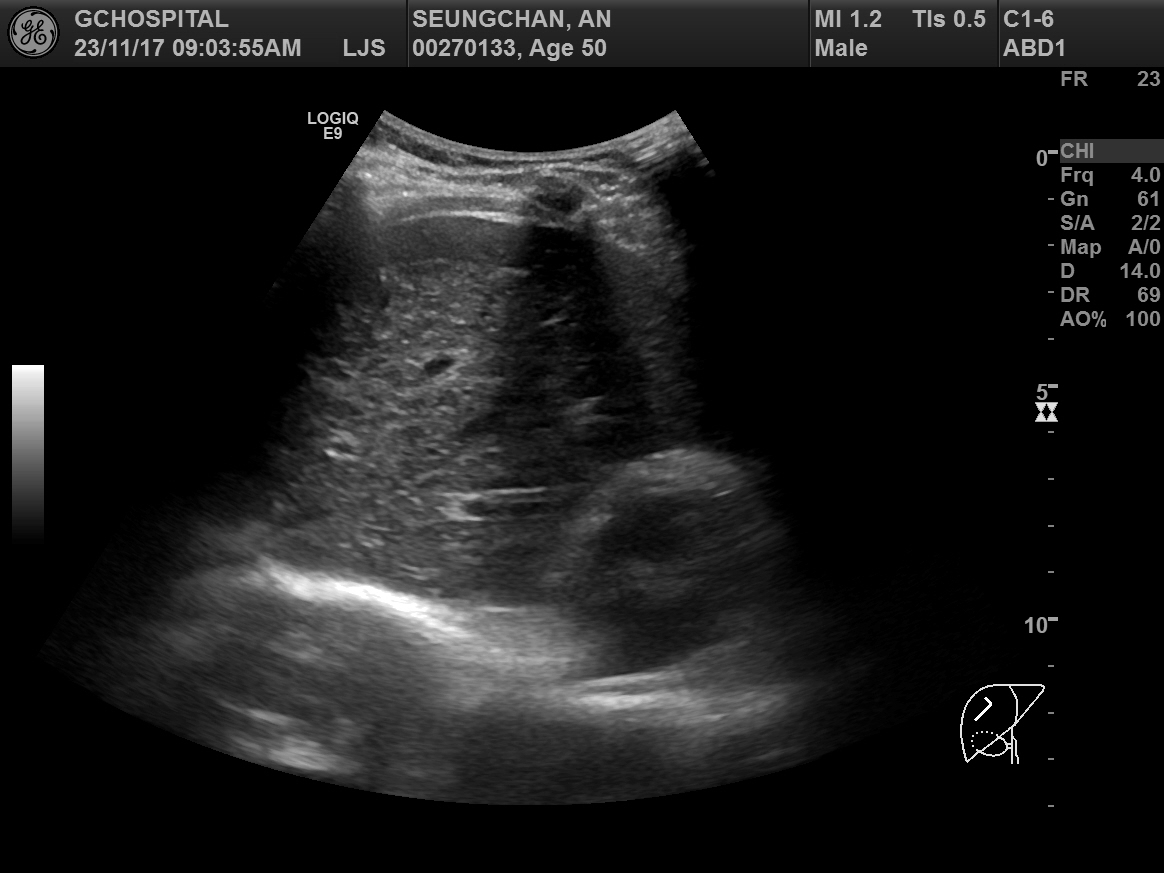

다음으로 중간정맥(middle hepatic vein)의 B모드 및 컬러도플러영상입니다. 컬러도플러영상에서 또렷하게 보이는 중간정맥이 B모드영상에서는 마찬가지로 매우 가늘고 희미하게 보입니다. 컬러도플러 영상에서 보여주는 중간정맥의 굵기가 실제 직경과는 차이가 있겠으나, B모드에서 보이는 것보다는 훨씬 직경이 클 것으로 보이며, B모드영상에서는 전혀 확인할 수 없었던 가지부분들도 컬러도플러영상에서는 또렷하게 확인됩니다.

간초음파를 시행하면서 확인해야 하는 표준영상 중에는 우간정맥의 장축을 포함하는 영상이 포함되어있습니다. 마찬가지로 간좌엽의 시상면영상을 확인할 때에도 좌간정맥(Lt. hepatic vein)이 포함되어 촬영하는 게 보통입니다. 그렇게 간정맥을 확인하는 과정에서 위와 같이 간정맥이 잘 보이지도 않고, 실제 직경보다 훨씬 작게 보이는 이런 현상은 현장에서는 굉장히 흔한 현상입니다.

B모드영상에서 간정맥이 실제보다 훨씬 얇고 희미하게 보이거나, 아예 잘 보이지 않는 이유는 간정맥의 혈관벽이 얇아서 초음파신호가 반사되지 않아 영상에서 혈관벽을 특정할 수 없기 때문입니다. 특히 간실질의 에코음영이 거칠거나 간섬유화가 심하게 진행된 만성 간질환 환자들에서 간정맥을 확인하지 못하거나, 굉장히 가늘게 보이는 경우가 많습니다.

위의 영상들은 모두 GE사의 logiq E9 장비를 통해 얻은 영상입니다. 혹시 몰라 tissue harmonic image모드를 꺼놓거나, 다른 영상옵션들을 조절해봐도, 간정맥이 실제보다 가늘거나 희미하게 보이는 환자분들에서 일반적인 B모드영상보다 간정맥을 더 또렷하게 보여주는건 불가능했습니다. 지난 17년 내내 GE사의 초음파장비만을 써와서 타사 장비들의 상황을 비교해보지 못했지만, 어쨋던 GE사의 장비들 만큼이라도 이런 한계점을 극복해서 더 나은 영상을 담보할 수 있게 발전했으면 좋겠습니다.

그런 장비의 발전과 진보가 있기 전까지는 간초음파의 표준영상을 얻는 과정에서 간정맥, 특히 우간정맥의 장축을 보여주는 영상을 촬영할 때에는 좀 더 번거롭더라도, 컬러도플러영상을 함께 촬영하면서 우간정맥을 확인하는 것도 좀 더 신뢰할만한 간초음파영상을 얻기 위해 권장될 수 있겠다는 생각입니다.